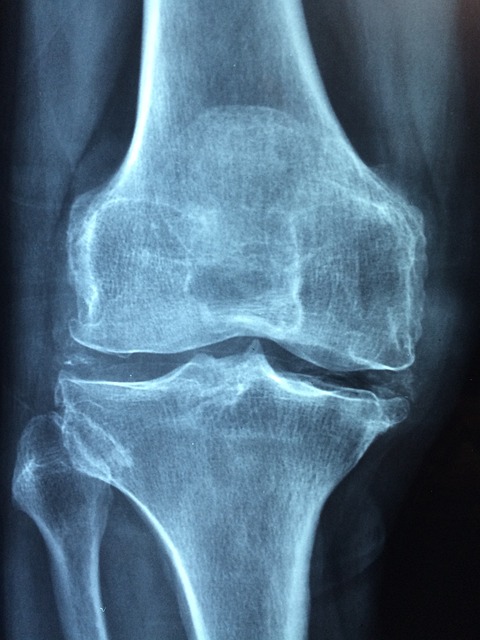

골다공증 예방은 생애 전 주기에 걸쳐 이루어져야 하며, 각 연령대별로 중점을 두어야 할 예방 전략이 다릅니다. 어린이와 청소년기는 뼈 형성이 가장 활발하게 이루어지는 시기로, 최대 골량(peak bone mass)을 높이는 것이 중요합니다. 최대 골량은 20대 중반까지 형성되며, 이 시기에 형성된 최대 골량이 높을수록 노년기 골다공증 위험이 낮아집니다. 따라서 성장기 아동과 청소년들은 충분한 칼슘과 비타민 D 섭취, 규칙적인 체중부하 운동을 통해 최대 골량을 높이는 데 중점을 두어야 합니다. 특히 이 시기에는 탄산음료나 패스트푸드와 같은 영양가 낮은 식품 대신, 칼슘이 풍부한 유제품과 다양한 과일, 채소를 충분히 섭취하는 것이 중요합니다. 또한 활발한 신체 활동과 규칙적인 운동 습관을 형성하는 것이 장기적인 뼈 건강에 도움이 됩니다. 성인기에는 최대 골량을 유지하고 골밀도 감소를 최소화하는 것이 중요합니다. 30대 중반부터 골밀도가 서서히 감소하기 시작하므로, 적절한 칼슘과 비타민 D 섭취, 규칙적인 체중부하 운동과 근력 운동을 통해 골밀도 감소를 늦추는 것이 중요합니다. 또한 흡연, 과도한 음주, 카페인 과다 섭취와 같은 골밀도에 부정적인 영향을 미치는 생활 습관을 개선하는 것도 필요합니다. 특히 여성의 경우 임신과 수유 기간에는 칼슘 요구량이 증가하므로, 이 시기에 충분한 칼슘 섭취가 중요합니다. 폐경기 여성은 에스트로겐 감소로 인해 골밀도 감소가 가속화되는 시기로, 골다공증 예방에 특별한 주의가 필요합니다. 폐경 후 5-7년 동안 전체 골량의 약 20%까지 손실될 수 있으므로, 이 시기에는 칼슘과 비타민 D 섭취를 더욱 늘리고, 규칙적인 체중부하 운동과 근력 운동을 통해 골밀도 감소를 최소화하는 것이 중요합니다. 필요에 따라 호르몬 대체 요법이나 골다공증 예방 약물 치료를 고려할 수도 있으며, 이는 의사와 상담 후 결정해야 합니다. 노년기에는 골밀도 유지와 함께 낙상 예방이 매우 중요합니다. 노년기에는 골밀도 감소와 함께 근력 약화, 균형 감각 저하, 시력 저하 등으로 인해 낙상 위험이 증가하며, 이로 인한 골절 위험도 높아집니다. 따라서 적절한 칼슘과 비타민 D 섭취, 안전한 체중부하 운동과 근력 운동을 통해 골밀도와 근력을 유지하고, 균형 운동을 통해 낙상 위험을 감소시키는 것이 중요합니다. 또한 가정 내 낙상 위험 요소를 제거하고, 필요시 보행 보조기구를 사용하는 등 낙상 예방을 위한 환경 조성도 필요합니다. 골다공증 위험이 높은 사람들은 정기적인 골밀도 검사를 통해 조기에 골감소증이나 골다공증을 발견하고 적절한 관리를 시작하는 것이 중요합니다. 일반적으로 65세 이상 여성과 70세 이상 남성, 폐경 후 여성 중 위험 요인이 있는 경우, 골절 경험이 있는 경우 등에서 골밀도 검사가 권장됩니다. 골밀도 검사는 이중에너지 X선 흡수계측법(DXA)을 통해 주로 척추와 고관절의 골밀도를 측정하며, T-점수가 -1.0 이상이면 정상, -1.0에서 -2.5 사이면 골감소증, -2.5 이하면 골다공증으로 진단됩니다. 골다공증 예방을 위한 식이 요법에서는 칼슘과 비타민 D 외에도 다양한 영양소를 균형 있게 섭취하는 것이 중요합니다. 단백질은 뼈 기질 형성에 필요하며, 적절한 단백질 섭취는 골밀도 유지에 도움이 됩니다. 그러나 과도한 단백질 섭취는 오히려 칼슘 배설을 증가시킬 수 있으므로 적정량을 섭취하는 것이 중요합니다. 마그네슘, 인, 아연, 구리, 망간 등의 미네랄과 비타민 K, 비타민 C 등도 뼈 건강에 중요한 역할을 합니다. 이러한 영양소들은 다양한 과일, 채소, 통곡물, 견과류 등을 통해 섭취할 수 있으며, 편중된 식습관보다는 균형 잡힌 식단을 통해 다양한 영양소를 섭취하는 것이 바람직합니다. 또한 소금, 카페인, 알코올 등은 칼슘 배설을 증가시키거나 칼슘 흡수를 방해할 수 있으므로 과도한 섭취를 피하는 것이 좋습니다.